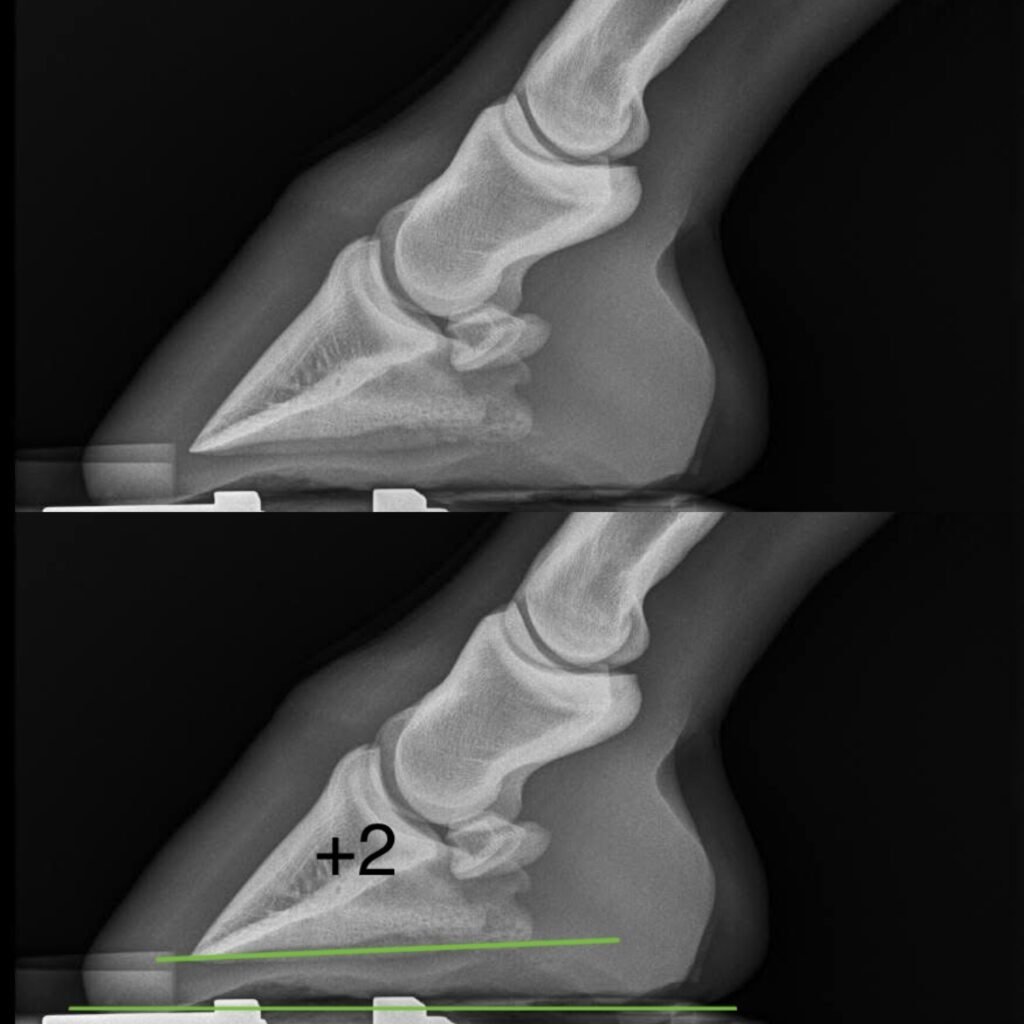

Hier rechts en onder zie je röntgenfoto’s met verschillende hoeken. De onderste groene lijn is de grondlijn, de bovenste groene lijn is de onderkant van het hoefbeentje. De graden staan erbij aangegeven. Kijk maar hoe anders de gewrichten op elkaar gestapeld staan bij de verschillende hoeken!